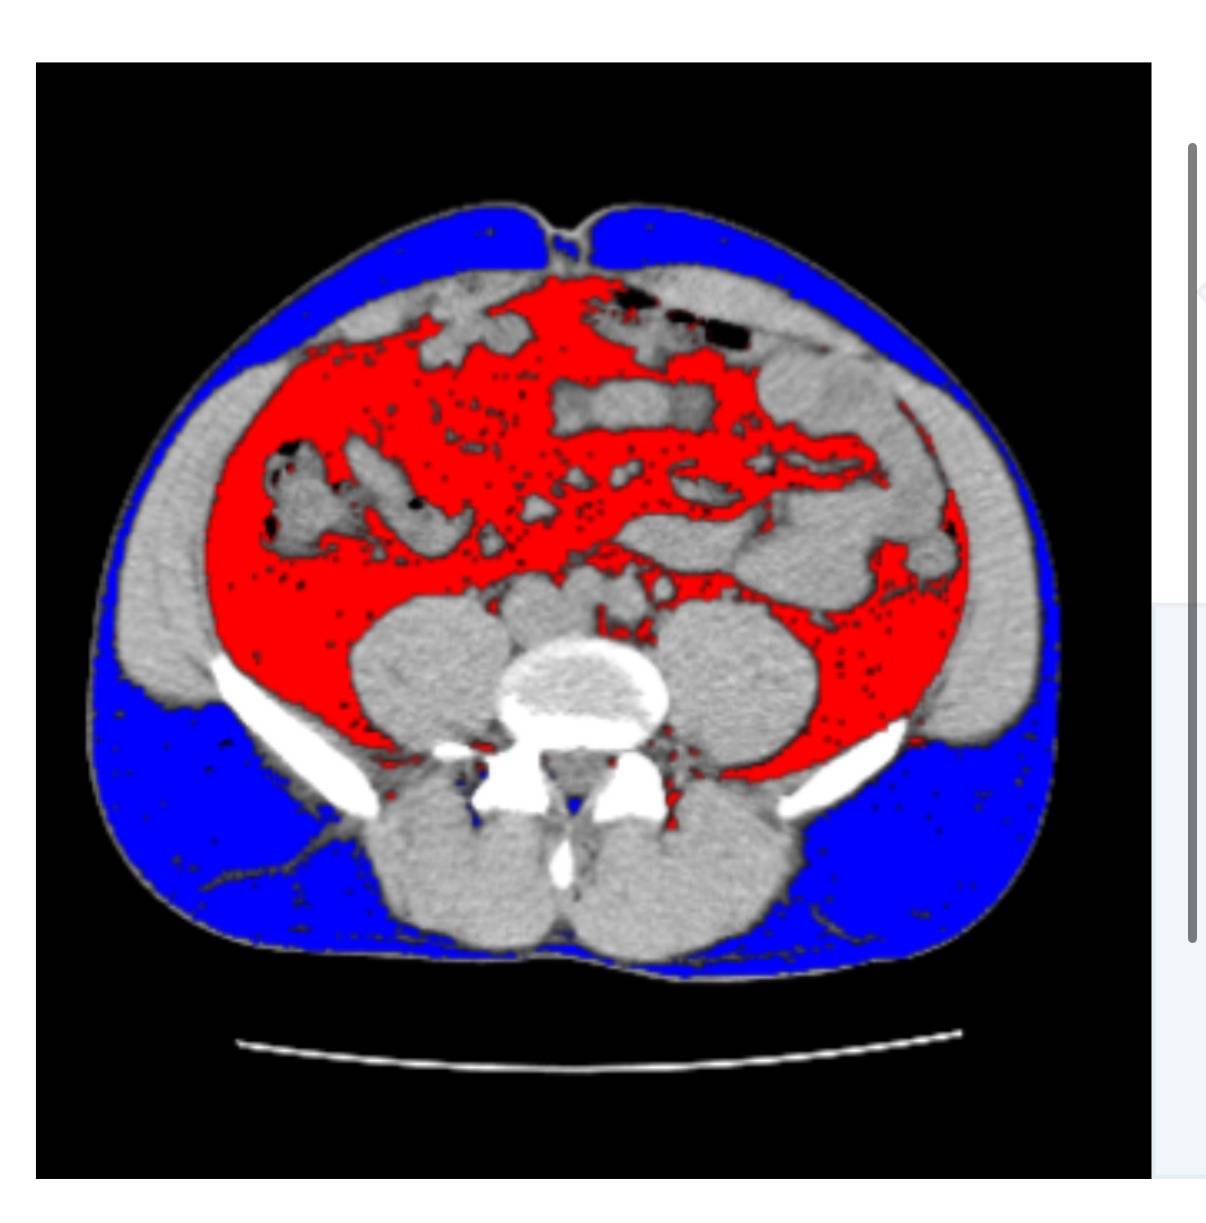

Fat Scanという、内臓脂肪CT検査があるのですが、

それをたまたまやってみると、それなりに内臓脂肪が・・

赤色:内臓脂肪

青色:皮下脂肪

現実を直視するというのは

辛いものです・・

内臓脂肪面積が100を超えると、多いですな・・となりますが

私は、125.1でしたね・・